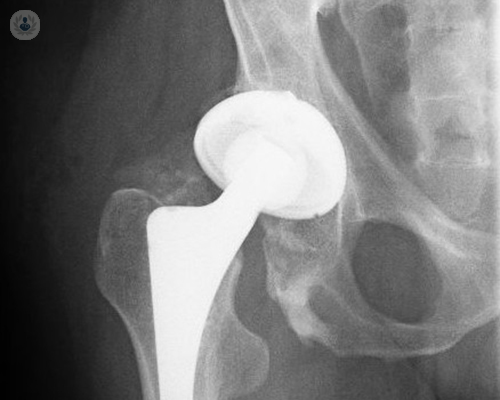

Reemplazo de cadera robótico de precisión submilimétrica: el nuevo estándar en recuperación y calidad de vida

La cirugía robótica permite una planificación personalizada y una ejecución con exactitud submilimétrica, mejorando la estabilidad, la seguridad y la recuperación funcional